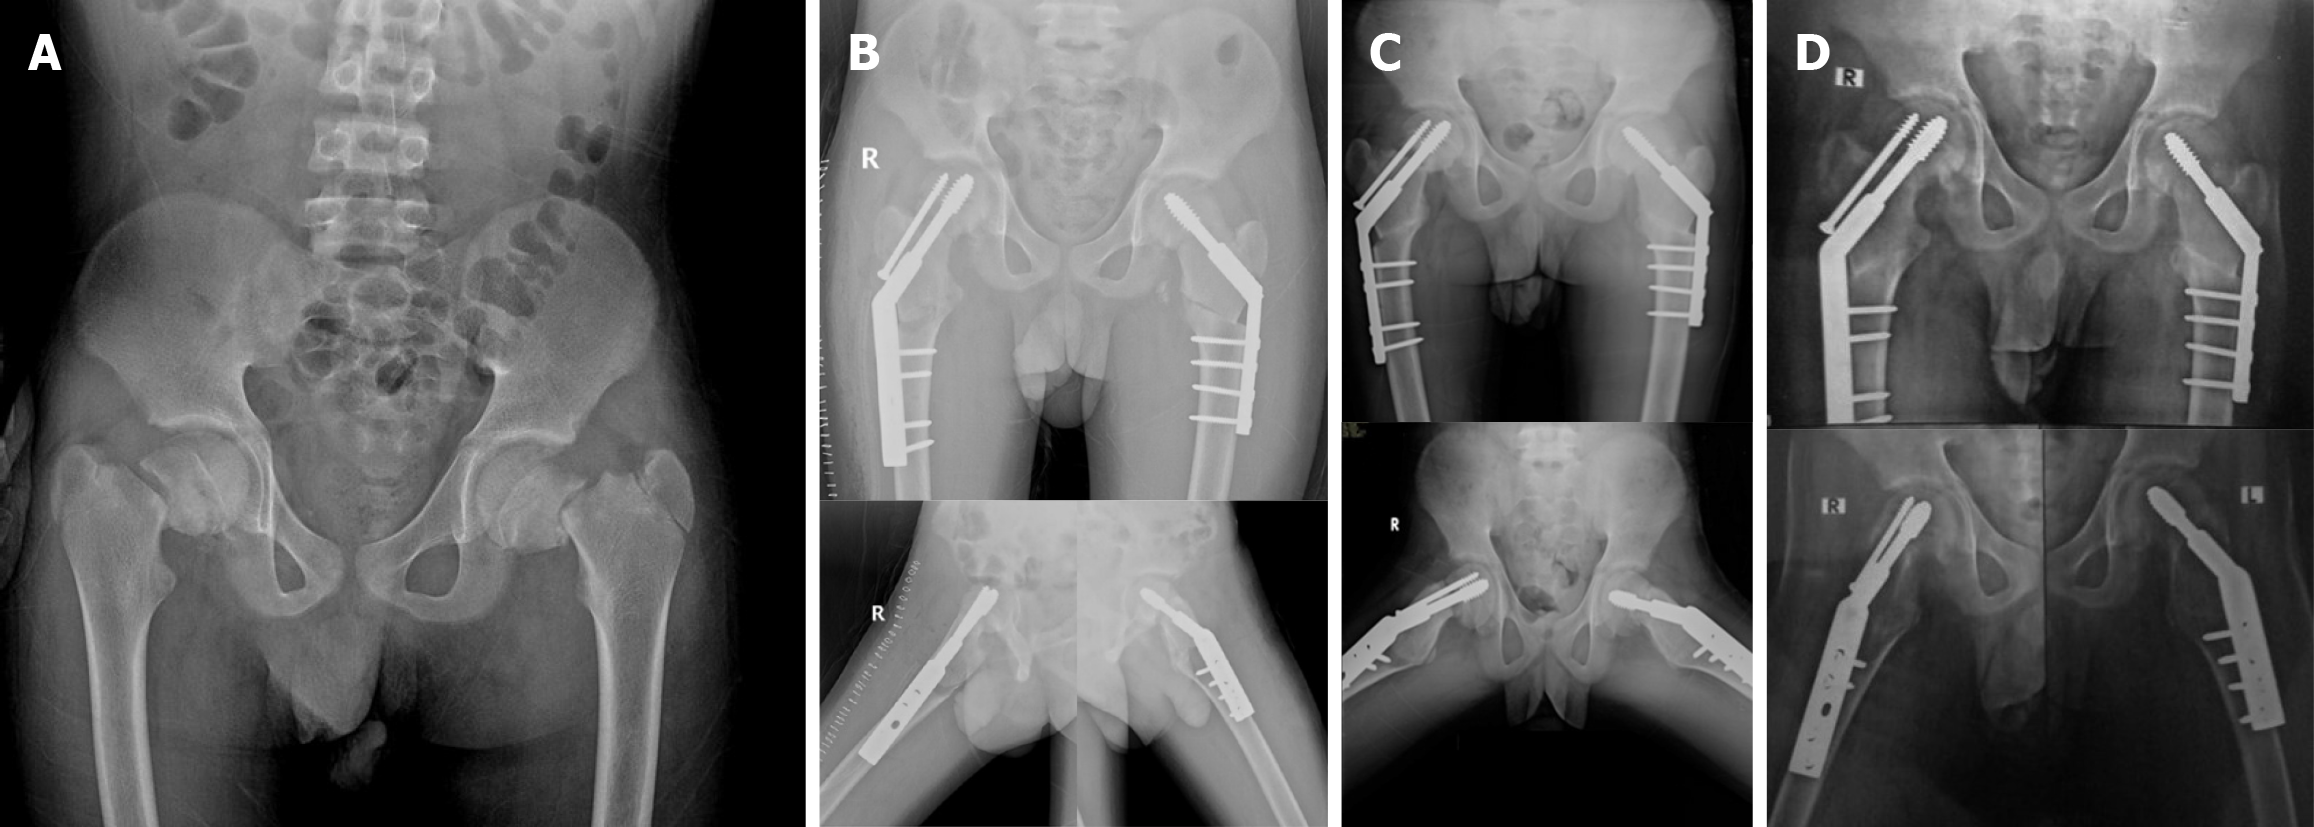

Figure 1 Radiographic series of a case with bilateral Delbet type II femoral neck fractures treated with staged bilateral sliding subtrochanteric valgus osteotomies.

A: Initial anteroposterior pelvis plain radiographs showed bilateral Delbet type II displaced femoral neck fractures; B: Early postoperative plain radiograph after staged bilateral sliding subtrochanteric valgus osteotomies fixed using 135° dynamic hip screw and partially threaded antirotation screws, immediately and 6 weeks after operating on the right and left hip; C: Plain radiographs obtained 6 months postoperatively showed acceptable bony union and intact femoral heads; D: Final plain radiographs at 18 months postoperatively showed complete union of both femoral neck fractures and the osteotomy sites.